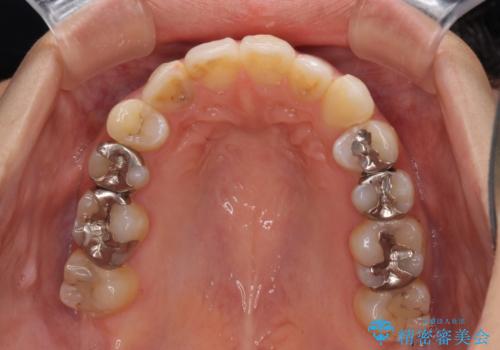

後戻りを治したい 骨格的なズレの大きい方のインビザライン矯正

- 中学生の時に矯正治療をしたものの、後戻りを気にして来院された患者様です。

骨格的に下顎が右側に変位しているため、左右の咬み合わせを理想的なものに改善することはできませんが、インビザラインにて歯列を整えることとしました。

骨格的なズレによる左右差は改善できませんでしたが、上下の正中を極力合わせるようにすることができました。